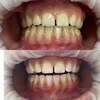

الدكتورة سيفيم شاكيليطاش طبيبة أسنان

مجالات التخصص

طب الأسنان

تقويم الأسنان